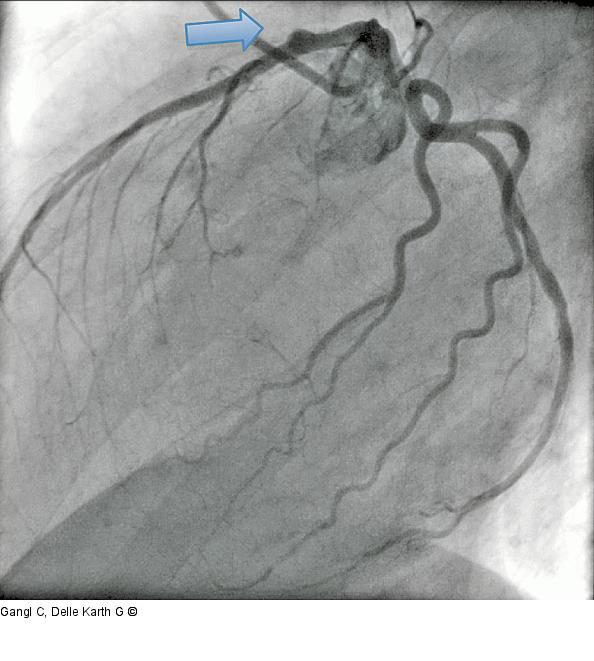

Abbildung 4: LAO

Aneurysmatische Ausbuchtung, LAO kaudal